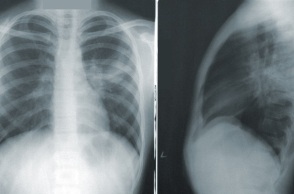

Η νέα πνευμονία «χτυπάει» κυρίως παιδιά

Την εκτίμηση ότι δεν χρήζει λόγος ανησυχίας για τη «μυστηριώδη» πνευμονία στην Κίνα εξέφρασε ο Δημήτρης Παρασκευής, σημειώνοντας ότι δεν θα έχουμε νέα πανδημία, καθώς εμφανίζεται κυρίως σε παιδιά.

Ο καθηγητής, επικαλούμενος πάντα στοιχεία που έχουν αναφέρει οι αρχές της Κίνας στον ΠΟΥ, επισημαίνει ότι πρόκειται για λοιμώξεις του αναπνευστικού, που εντοπίζονται κυρίως σε παιδιά και αφορούν γνωστά παθογόνα, τα οποία κυκλοφορούν αυτή την περίοδο, όπως ο ιός της γρίπης, ο RSV, ή ο Sars- Cov2.

Αυτό το οποίο μάλλον έχει συμβεί στην Κίνα, διευκρινίζει, είναι αυτό που συνέβη στον υπόλοιπο κόσμο το φθινόπωρο του 2022: «Λόγω της παύσης των περιοριστικών μέτρων για τον κορωνοϊό, είχαμε αυξημένη κυκλοφορία των αναπνευστικών ιών, με έμφαση στα παιδιά, τα οποία δεν είχαν εκτεθεί σε αυτά τα παθογόνα, τα προηγούμενα δύο έτη».